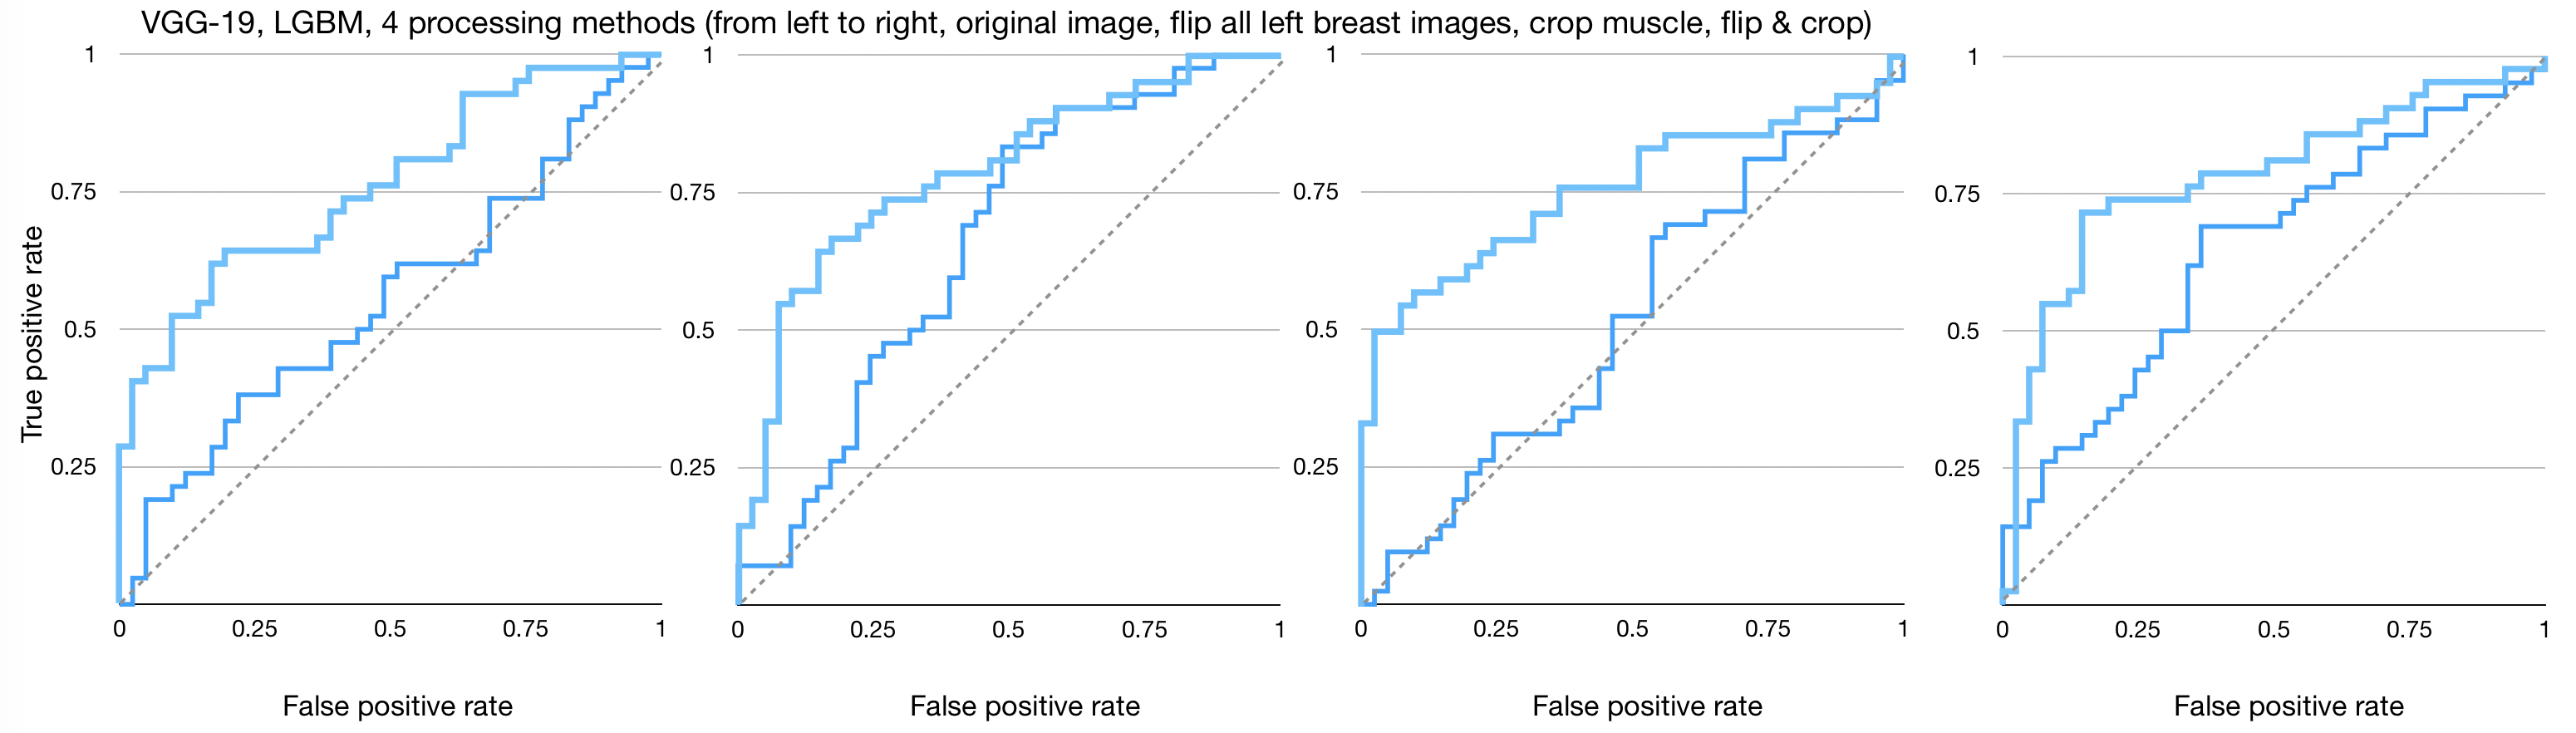

Figures 4, 5, and 6 show the imaging for which both humans and CNNs make mistakes, model introduced errors, and model corrected human errors. Figure 7 shows the receiver operating characteristic curve (ROC curve) for each of the 16 end-to-end models between the CNNs and radiologist gist plus CNNs. Tables 1 and 2 show the AUC data and differences used in the main text from the 16 conditions we have tested. Although the present work provides knowledge about adding radiologists’ data into CNN, it does not allow for training on new data, thus restricting our application domain to a small range of in-house data.